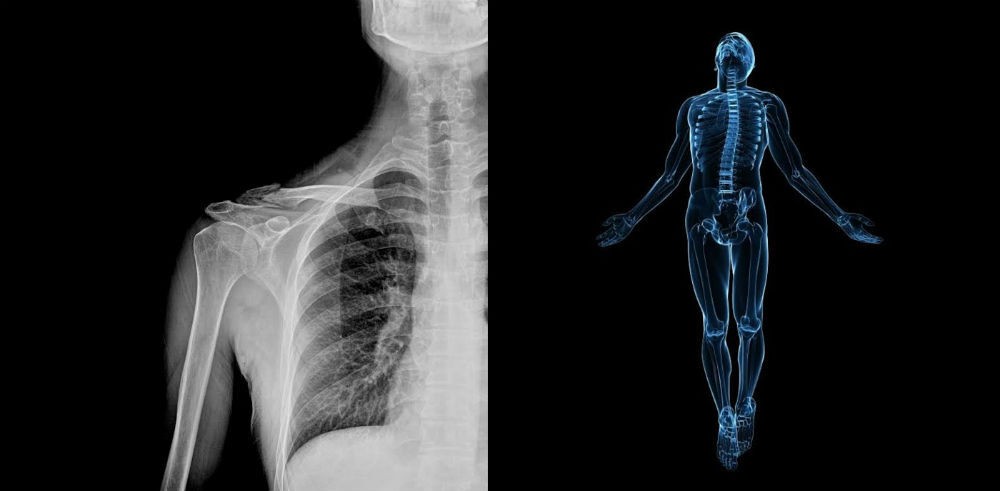

Precisamente este tipo de Inteligencia Artificial es la que están probando en el Zebra Medical Imaging en colaboración con Intermountain, los cuales están creando una red neuronal capaz de estudiar y comparar radiografías en su propia base de datos. Un proceso que, esencialmente, es el que lleva a cabo un radiólogo especializado cada vez que echa un ojo a una radiografía.

En este caso lo que se pretende es enviar la prueba de imagen directamente a esta IA capaz de interpretar radiografías, sin pasar por el posible error humano, ya que nos encontraríamos frente a un ordenador equipado de una potente base de datos. Además, esta IA estaría equipada con sugerencias para los radiólogos, reduciendo así todavía más la posibilidad de error.

Con el tiempo, este equipo de investigadores esperan que su IA pueda tener un mejor acceso a los diagnósticos médicos, especialmente en aquellos países donde escasean los profesionales sanitarios y especialistas médicos. Por el momento su IA capaz de interpretar radiografías se ha centrado en lesiones óseas, pero creen que también podrá ayudar en diagnósticos cardíacos y pulmonares.